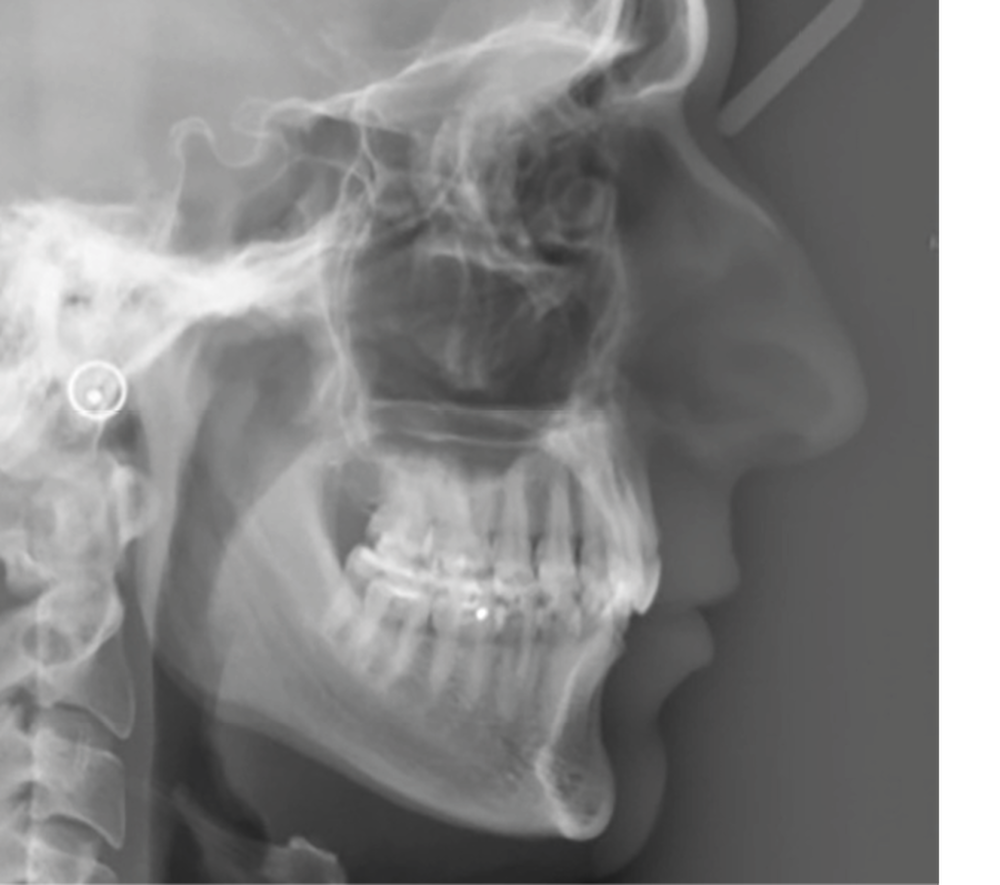

Examens complémentaires (fig. 3)

La téléradiographie de profil et l’analyse céphalométrique montrent une classe I squelettique tendance classe II dans un contexte d’hypodivergence, caractéristique des classes II division 2 [3,4]. L’axe de l’incisive mandibulaire est correct, au sein d’une symphyse épaisse, tandis que l’incisive maxillaire présente une rétroalvéolie importante. La supraclusion antérieure est d’origine mixte, majoritairement mandibulaire, en lien avec une courbe de Spee marquée.